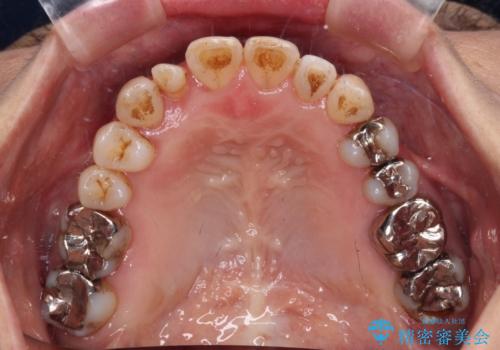

- 前歯の反対咬合を気にして来院された患者様です。

上顎骨の幅が下顎骨よりも小さいので、拡大装置により骨幅を広げて上下関係を改善すると同時にワイヤー矯正で反対咬合の改善を図り、その後インビザラインにて歯並びを整えることとしました。

上顎前歯の矮小歯は矯正治療の途中でオールセラミッククラウンを装着し、左右のバランスを整えることとしました。

急速拡大装置の使用により奥歯の咬み合わせが劇的に変わり、その変化を利用して反対咬合を改善することができました。

治療期間中は奥歯が咬み合わず、食事が取りにくいなどの不都合がありましたが、最終的にはきれいに整えることができました。